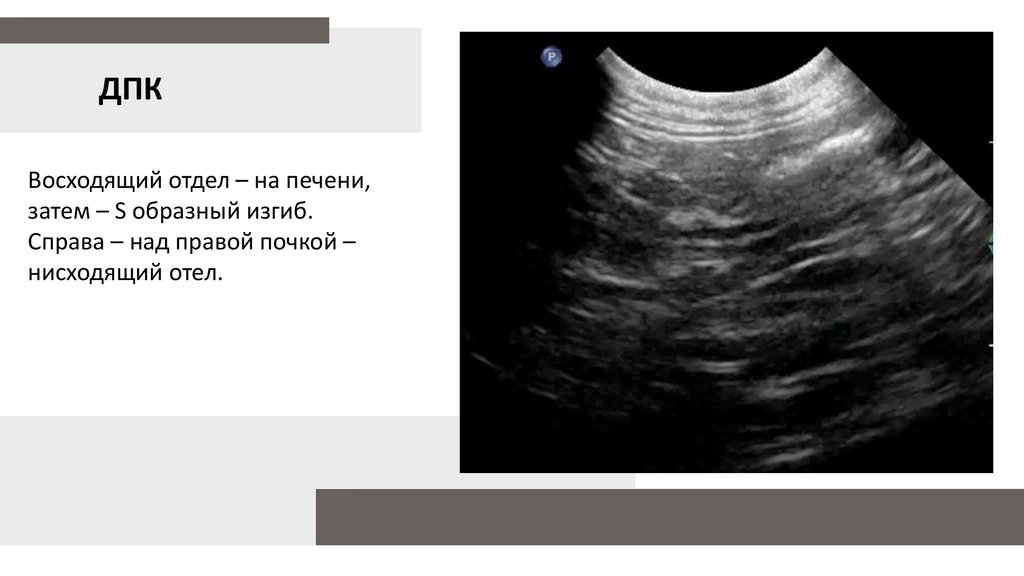

ДПК

Восходящий отдел – на печени,

затем – S образный изгиб.

Справа – над правой почкой –

нисходящий отел.